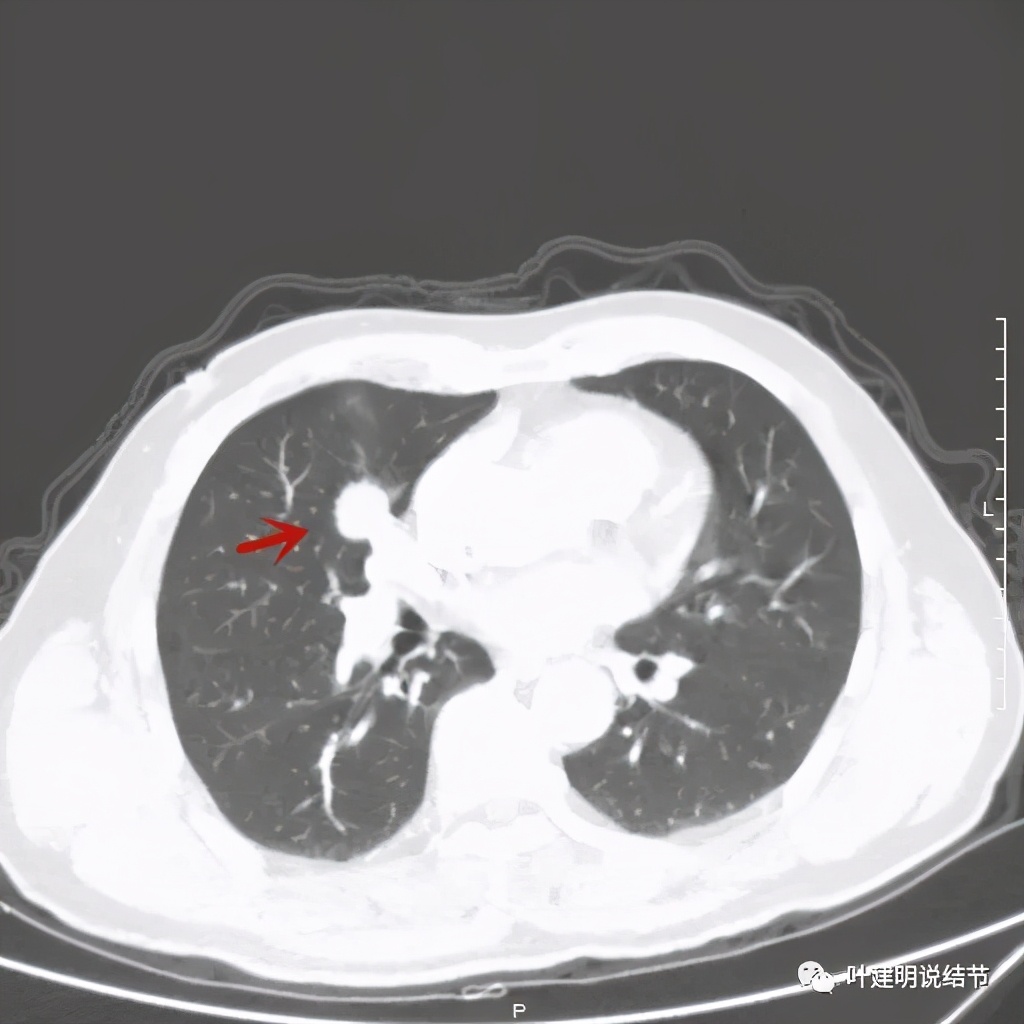

那么当时的胸部影像又是如何的呢?

以上几图示病灶膨胀感明显,无卫星灶,周围无渗出性改变

上图绿色箭头示支气管通气征